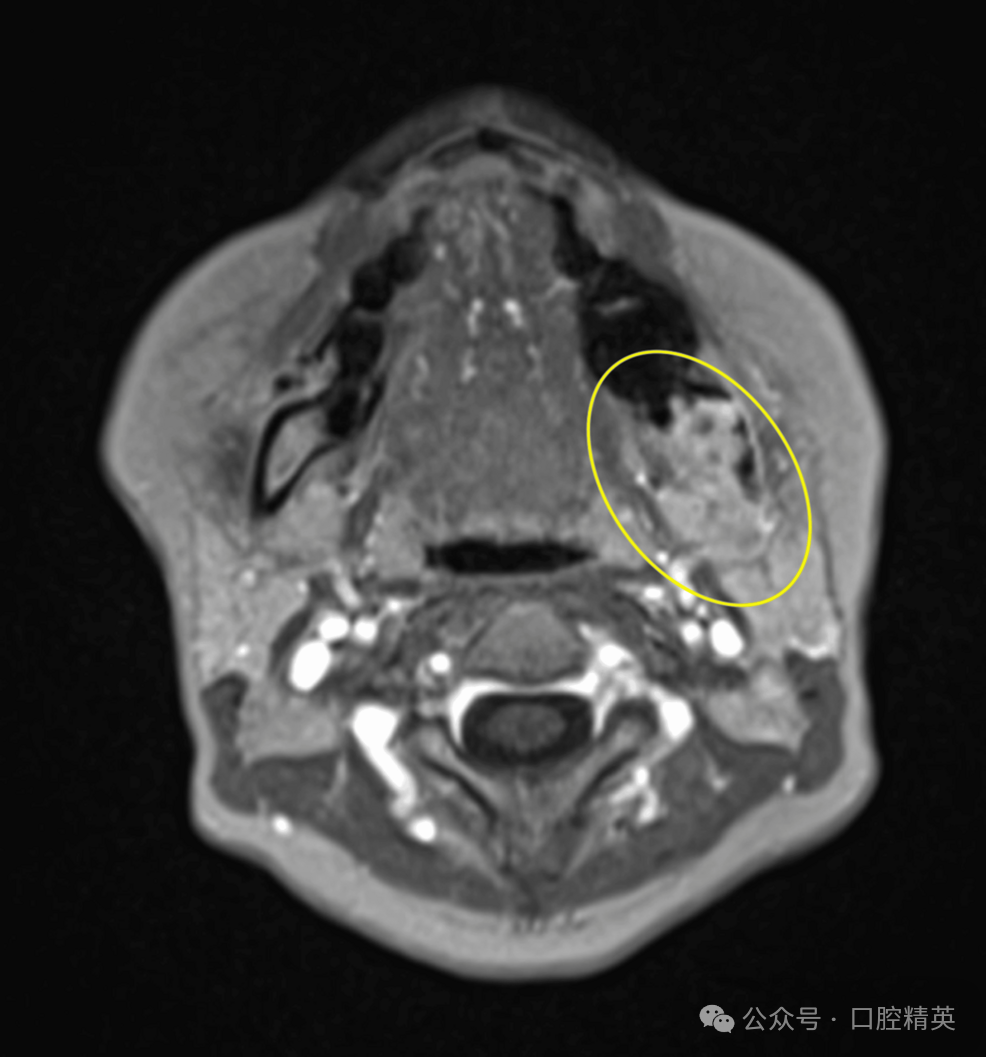

2017年3月,一名53岁女性因左下第三磨牙区疼痛就诊于当地牙科诊所,临床诊断为左下第三磨牙冠周炎,转诊至我科拟行拔牙术。初诊时,患者口外检查未见异常;口内检查见左下磨牙区牙龈红肿,左下第三磨牙(38)完全阻生。曲面体层片显示36、37牙根尖区可见少许低密度影,但38周围无明显异常(图1)。

图1 初诊曲面体层片

可见36、37根尖区少许低密度影,38周围无显著异常(黄圈所示)。